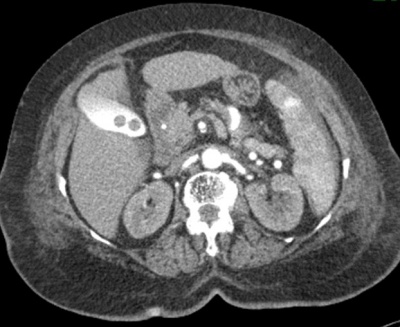

במעבדה אין מאפיינים מיוחדים. האבחנה מתבצעת על-ידי בדיקת אולטרה-סאונד, שהיא בדיקת בחירה לאבחון אבנים בכיס המרה בשל היותה בדיקה בלתי פולשנית בעלת אמינות גבוהה. בבדיקת האולטרה-סאונד יודגמו אבנים בכיס המרה ככתמים בהירים בתוך הכיס, הנעים בשינוי תנוחה. מאחוריהם ניתן לראות את הצל האקוסטי (Acoustic shadow) (תצלום 19.8). שני ממצאים אלה הם הסימנים המובהקים לאבני מרה. בבדיקה זו אפשר לבדוק את קוטר דרכי המרה החוץ-כבדיות. רק 20% מהאבנים בדרכי המרה מודגמות בשיטה זו. כמו-כן אפשר למדוד את קוטר כיס המרה ואורכו. בדיקות אלה אמינות ב- 94%-90%. לעיתים האבנים אינן נראות בברור ב- US אבל נראות ב- אולטרה-סאונד אנדוסקופי (EUS) או מאובחנות ב- CT (תצלום 20.8).